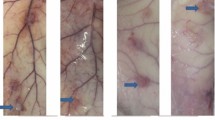

Gross histology

Gross observation showed the translucent and elastic membrane was formed around PMMA (Fig. 1f). In the control group, there was no membrane formation but callus tissue surrounding with connective tissue. The induced membrane (Fixation group and Non-fixation group) and connective tissue (control group) was removed completely for further testing. As shown in Fig. 5, H&E staining revealed an intensive fibrous, cell-rich, and vascularized tissue in PMMA groups (Fixation group and Non-fixation group), while just little vessel like structure was observed in control group. Compared with membrane in Non-fixation group, there were more micro-vessels in Fixation group. And with the extending of implantation time, the micro-vessels had a tendency to increase and to be more mature. The osteogenesis activity was assessed via Alizarin red staining for calcium deposition (Fig. 6). The quantitative analysis of calcification showed that the reaction of calcifying nodules in Fixation group and Non-fixation group was significantly higher than that of the control group, indicating significant osteogenic activity around PMMA. And the amount of calcification in Fixation group was significantly more than that in Non-fixation group in 4 weeks and 6 weeks after operation (Fig. 7).

Representative H&E staining of Masquelet membrane (scale bar: 100 mm). H&E staining shown that the intensive fibrous, cell-rich, and vascularized tissue (white arrow) were formed in Fixation group (a) and Non-fixation group (c), while just little vessel like structure was observed in control group (e), in 4 weeks postoperatively. The micro-vessels had a tendency to increase and to be more mature in Fixation group (b) and Non-fixation group (d), while still little in control group (f), in 6 weeks postoperatively.